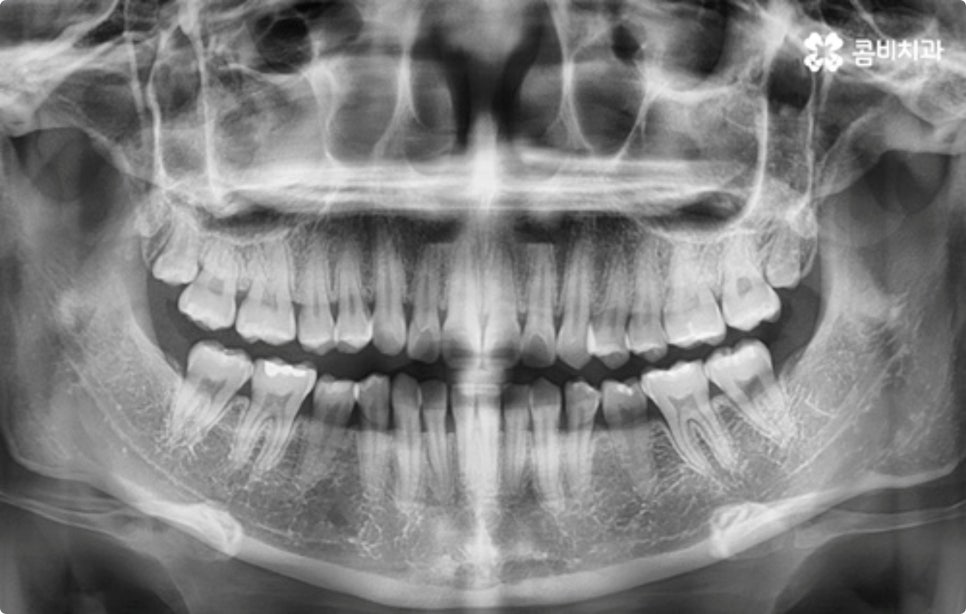

이때 구강 내부는 물론 눈으로 확인하기 어려운 상하악 구조까지 세밀하게 체크하는 3D CT 와 교정 후 모습을 예측하여 보다 안정적으로 교정 플랜을 세울 수 있도록 도와주는 모르페우스 같은 정밀 진단 장비를 갖추고 있는 치과를 찾아 검진을 받는 게 중요한 포인트라고 할 수 있습니다.

클리피씨 교정도 치아 색상의 세라믹 재질을 사용하기 때문에 심미성이 높은 편이지만 만약에 장치가 아예 겉으로 드러나지 않았으면 좋겠다고 생각하신다면 브라켓을 치아 안쪽에 부착하는 설측교정을 이용할 수 있는데요. 하지만 설측교정은 혀와 맞닿는 부분의 이물감, 통증, 발음상 문제 등을 일으킬 수 있기 때문에 잘 보이는 윗니는 설측으로, 잘 드러나지 않는 아랫니는 보통 교정과 같이 순측 (입술쪽) 으로 진행하는 콤비교정을 통해 이를 보완할 수 있어요. 사진에서 살펴보실 수 있는 케이스 역시 이렇게 콤비로 진행한 직장인치아교정 과정으로 시간이 지날수록 점차 치열이 가지런해지고 교합이 올바르게 개선되는 것을 확인해 보실 수 있습니다.